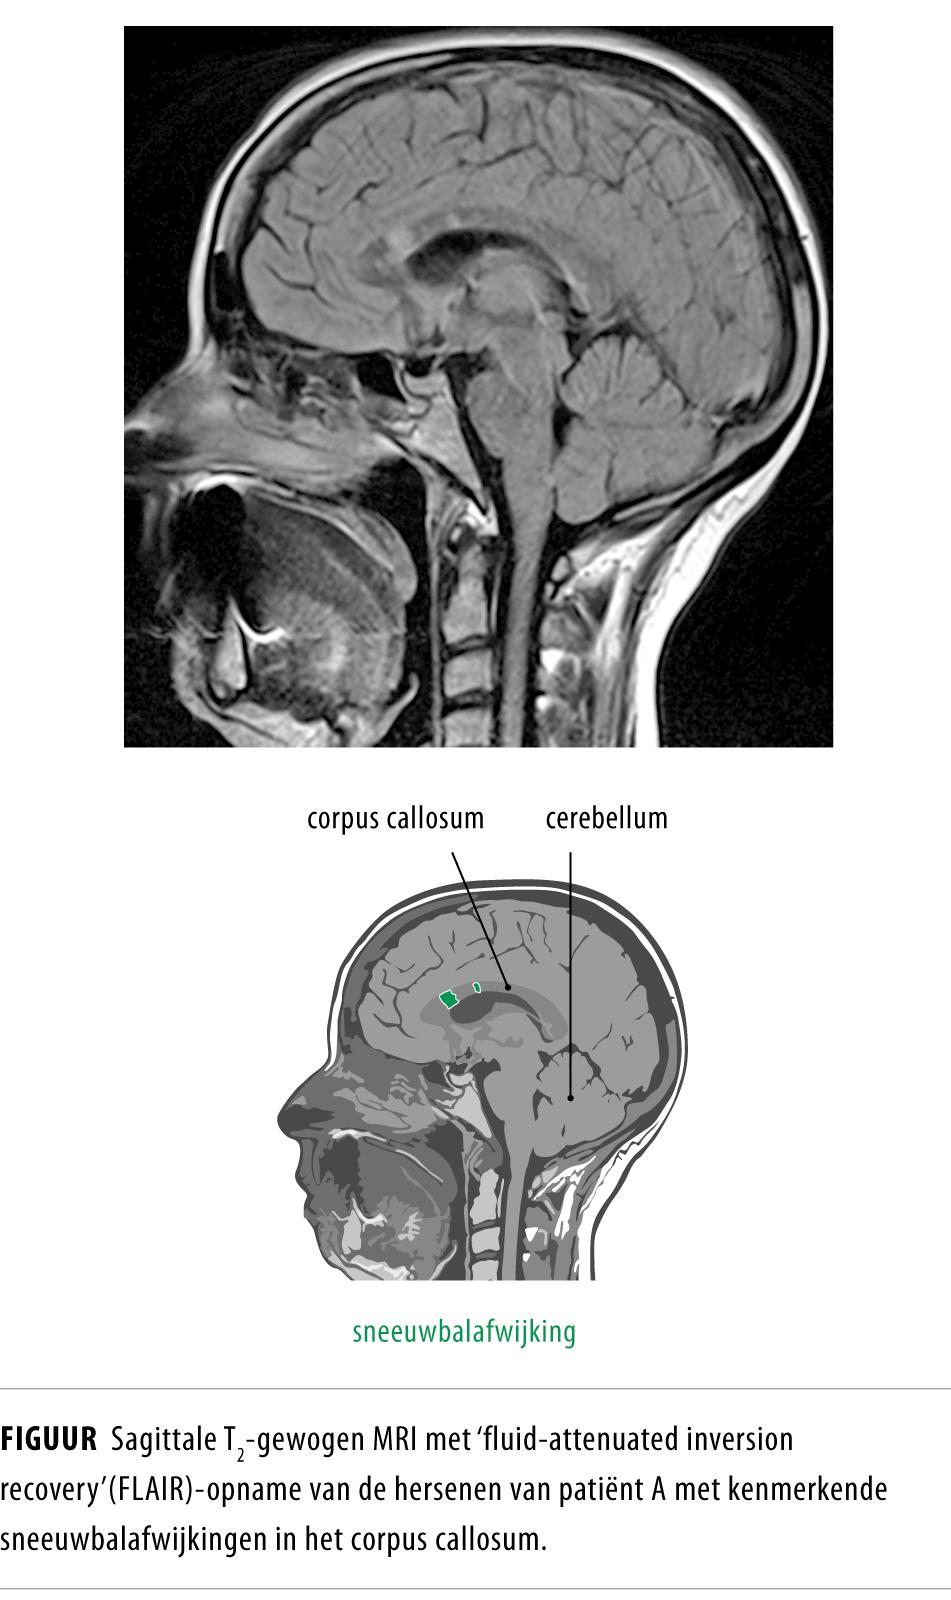

Het syndroom van Susac is een zeldzame angiopathie die wordt gekenmerkt door de trias van encefalopathie, gehoorvermindering en retinale vaatocclusies. De diagnose wordt gesteld op basis van het klinisch beeld, een MRI-scan van het cerebrum, audiometrie, fundoscopie en fluorescentieangiografie. Snelle, intensieve en langdurige behandeling met immunosuppressiva, immunoglobulinen, plasmaferese of anticoagulantia kan leiden tot gehele of gedeeltelijke remissie.

Een 31-jarige vrouw raakte toenemend verward tijdens een vakantie op Aruba. Bij terugkeer in Nederland werd zij opgenomen met een psychotisch beeld. Vanwege de atypische psychiatrische klachten en de subtiele afwijkingen bij het neurologisch onderzoek werd uitgebreid somatisch onderzoek verricht. Er werden onder andere typische afwijkingen gevonden in het corpus callosum op de MRI-scan van het cerebrum. Na behandeling met immunosuppressiva verdwenen de psychotische klachten.